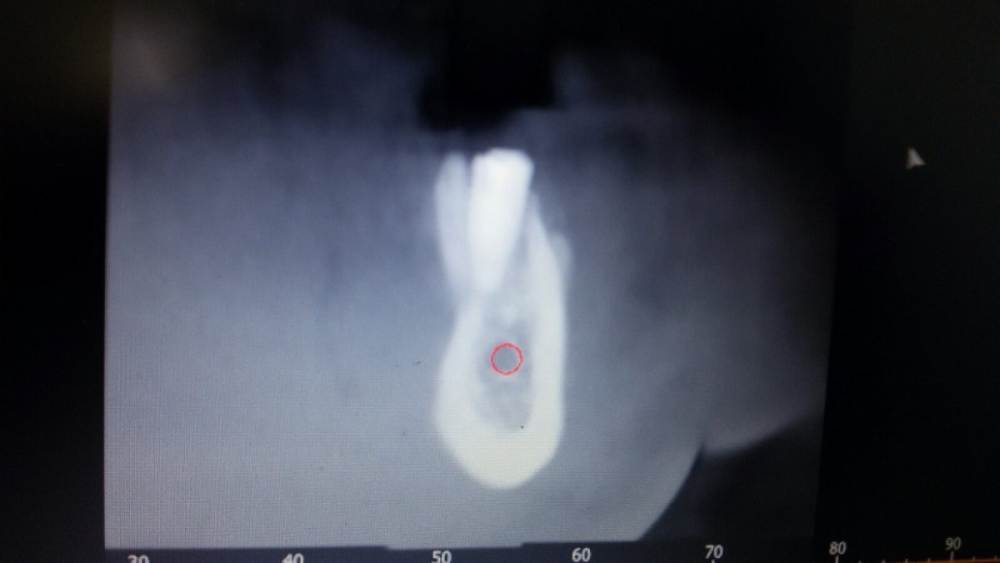

chealena Опубликовано 14 августа, 2021 Поделиться Опубликовано 14 августа, 2021 Здравствуйте ! В среду мне установили 4 импланта по две на каждые стороны нижние, слева также удаляли зуб и туда сразу ставили имплант. После этого у меня сейчас онемевшая губа и часть зубов и часть подбородка, что мне делать? Врач говорит что все нормально и нерв не был задет, а я вижу что на кт снимке идёт траншея до нерва , как будто он просверлил туда. Говорит мне ничего не делать и просто ждать. Но онемение не проходит, уже и отёк спал , а онемение есть и это ужасно противно, и когда пальцем вожу по этому месту очень неприятно как будто песок. Зуб слева первый имплант на снимке. Подскажите пожалуйста что делать! Ссылка на комментарий

Irouil Опубликовано 14 августа, 2021 Поделиться Опубликовано 14 августа, 2021 Как и что могло случится - это спрашивать стоит только у того человека, который видел своими глазами что и как случалось. Иначе говоря, эти вопросы надо задавать лечащему врачу. Выкручивание имплантов, судя по предоставленным снимкам, никак не повлияет на ситуацию с онемением. Но это не отменяет Вашей симптоматики, а значит какое-то влияние на нерв есть. Неврологическая терапия поможет снизить это влияние и ускорить процесс восстановления чувствительности. Ссылка на комментарий

Irouil Опубликовано 16 августа, 2021 Поделиться Опубликовано 16 августа, 2021 15.08.2021 в 00:45, chealena сказал: Но если нерв не поврежден почему у меня пол губы немые вместе с подбородком и частью зубов? Воздействия на нерв не ограничиваются только его повреждениями. Даже отёк от проведённой операции способен создать иногда достаточную компрессию чтобы вызвать транзиторную парестезию. Импланты в канал не пенетрируют, это самое главное. Руками хирурга тут особо нечего изменить/исправить. Применение физиотерапевтических процедур может ускорить реабилитацию. 2 Ссылка на комментарий